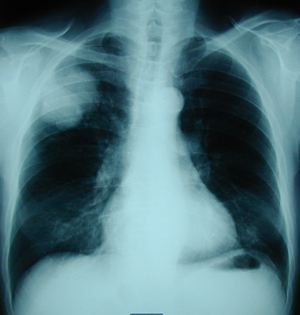

Figure 1

Postero-anterior chest X-ray that reveals the existence of a shadow in the right lung, of a male patient heavy smoker.